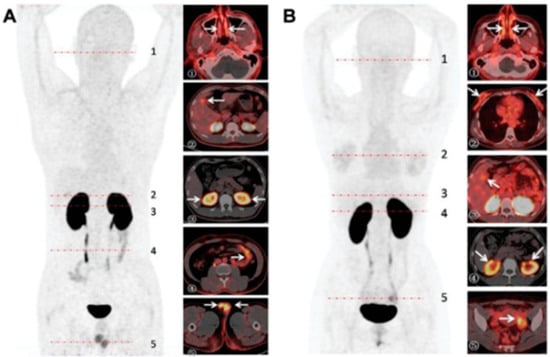

- Ren, F.; Jiang, H.; Shi, L.; Zhang, L.; Li, X.; Lu, Q.; Li, Q. (68)Ga-cyc-DX600 PET/CT in ACE2-targeted tumor imaging. Eur. J. Nucl. Med. Mol. Imaging 2023, 50, 2056–2067. [Google Scholar] [CrossRef]